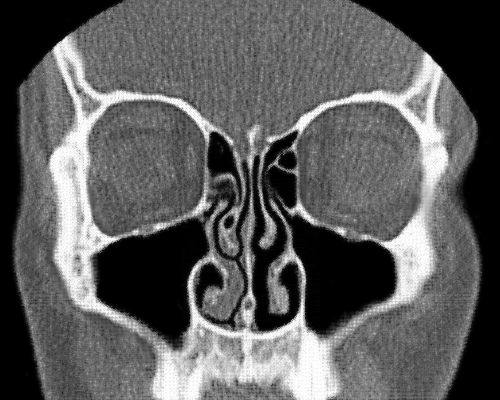

Tomografía que muestra la vía aérea más abierta a la derecha, y los cornetes hinchados que congestionan la izquierda.

Las fosas nasales toman turnos para respirar, en ciclos que duran en torno a dos horas y media. Los plexos que cubren los cornetes forman un tejido eréctil, como el pene y el clítoris, y los de un lado se llenan de sangre mientras que los opuestos se descongestionan al ser desviada la sangre.